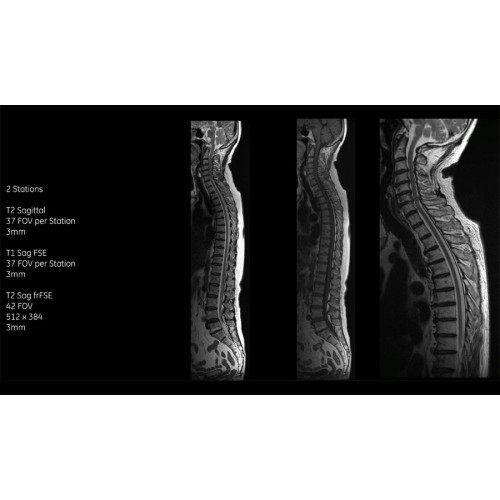

МРТ аппарат GE SIGNA Voyager 1.5T позволяет проводить полный спектр магнитно-резонансных исследований, включая нейровизуализацию, исследования опорно-двигательного аппарата, органов брюшной полости и малого таза, а также специализированные кардиологические программы.

• Неврология и нейрохирургия